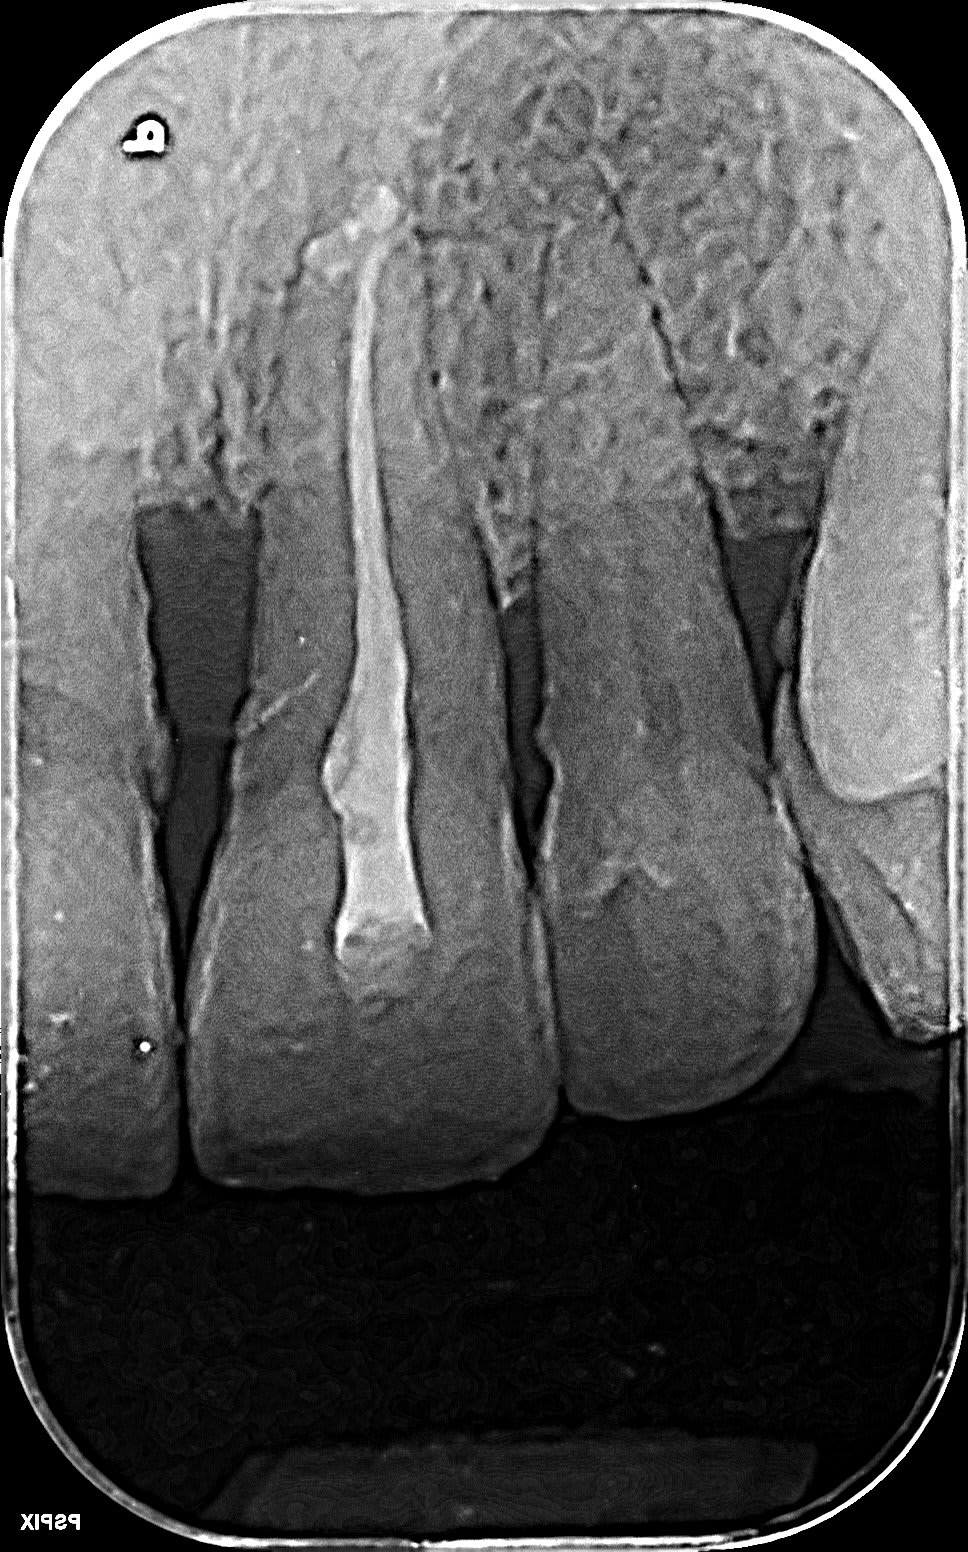

Je n'avais pas vu la pathologie interne.

Resor2 spbe02 - Eugenol